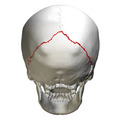

The lambdoid suture (or lambdoidal suture) is a dense, fibrous connective tissue joint on the posterior aspect of the skull that connects the parietal bones with the occipital bone. It is continuous with the occipitomastoid suture.

Its name comes from its uppercase lambda-like shape.

At birth, the bones of the skull do not meet. If certain bones of the skull grow too fast, then craniosynostosis (premature closure of the sutures) may occur. This can result in skull deformities. If the lambdoid suture closes too soon on one side, the skull will appear twisted and asymmetrical, a condition called "plagiocephaly". Plagiocephaly refers to the shape and not the condition. The condition is craniosynostosis.

The lambdoidal suture articulates with the occipital bone and parietal bones.